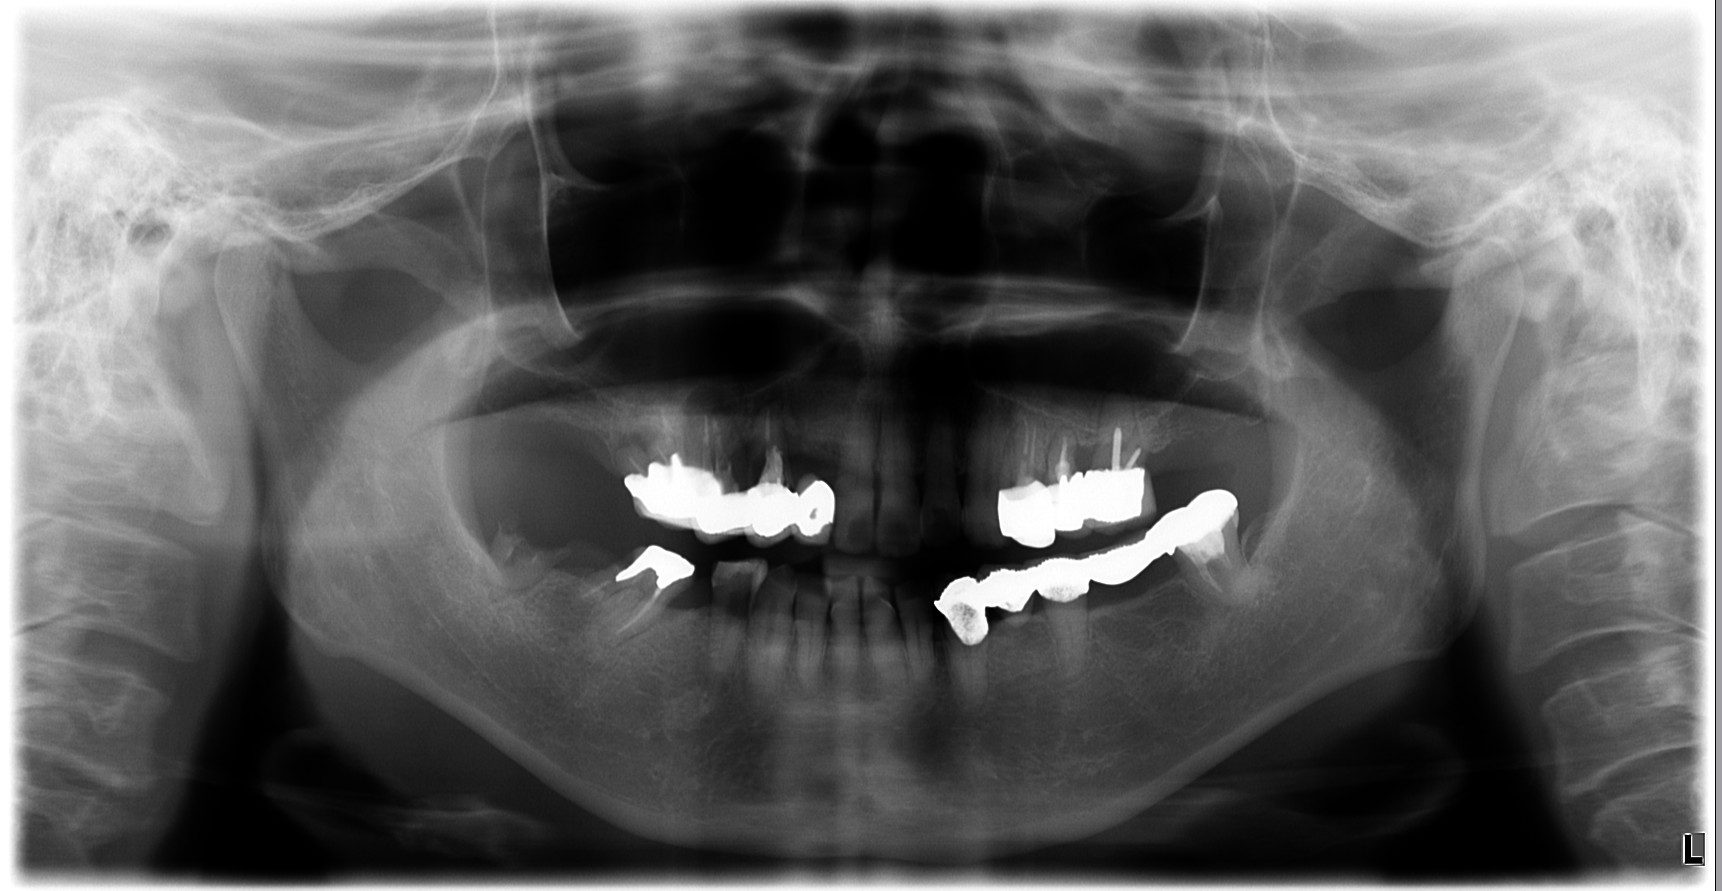

治療前

| 治療内容 | 初診時の考え方:原因は「歯」だけではなく“設計”のことがある 腫れや動揺があると、「歯周病だから」「根が悪いから」と言われがちですが、再治療で大切なのは なぜその状態まで進んだのかを整理することです。 補綴(被せ物・ブリッジ等)の設計や噛み合わせに無理があると、特定部位に力が集中して • 炎症(腫れ・排膿) • 動揺(グラつき) • 噛めない という状態に進行することがあります。 このケースも、力のかかり方を見直し、噛み合わせと補綴設計を再構成することが治療の軸になりました。 ⸻ 奥歯が噛めない → 前歯が働きすぎて切端咬合になっていた 患者様は「奥歯で噛めない」状態を補うように、前方で噛む癖がつき、 切端咬合(前歯同士がぶつかる噛み方)になっていました。 切端咬合は、 • 前歯が欠けやすい/すり減りやすい • 補綴が壊れやすい • 力の逃げ場がなくなる など、治療後の安定を難しくする要因になります。 そのため今回は、インプラント治療だけで完結させるのではなく、前歯の噛み合わせも作り直す必要がありました。 ⸻ 治療方針:本数を増やすのではなく“成立させる条件”を整える 患者様の条件(費用・怖さ・体の負担)を踏まえ、当院では • インプラントは3本に絞る • 上下ともにインプラントブリッジで噛める機能を回復 • 部分矯正で切端咬合を改善し、少ない本数でも成立する咬合へ • 可能な範囲で抜歯即時を選択し、外科を1回にまとめる という方針を採用しました。 ⸻ 治療のポイント①:部分矯正は“見た目”ではなく、設計を成立させるために使う 本数を絞った設計を成立させるには、力のかけ方(咬合設計)を整えることが重要です。 そこで、部分矯正で • 前歯の被蓋(かみ合わせ)を再構築 • 前歯に負担が集中しない状態へ • ブリッジに無理が出ない噛み合わせへ と調整し、少ない本数でも長期安定を狙える条件に近づけました。 ⸻ 治療のポイント②:上下インプラントブリッジ+材料選択(高強度ジルコニア) 上下ともにブリッジ設計の場合、材料と厚みの設計が安定性に直結します。 今回は、審美性や立体感はやや制限される可能性がある一方で、 強度を優先できる高強度ジルコニアを選択し、必要な厚みを確保しました。 「見た目の理想」よりも、まずは 噛めること/壊れにくいこと/長く使えること を優先した設計です。 ⸻ 治療のポイント③:抜歯即時で外科は1回にまとめる 患者様の「手術が怖い」「回数を減らしたい」という希望に対して、 感染や骨の条件を見極めたうえで、可能な範囲で抜歯と同日にインプラント埋入(抜歯即時)を行い、外科介入を1回にまとめました。 ※抜歯即時は、すべてのケースに適応できる方法ではありません。 ⸻ 治療後の経過(結果) • 噛めない状態が改善し、食事の不安が軽減 • 切端咬合を改善し、前歯の負担を減らす方向へ • 少ない本数でも成立するよう、噛み合わせと設計を最優先で再構成 ⸻ 担当医コメント 「理想形」だけを追うと、治療は大きくなりがちです。 今回のように、患者様の希望(負担・回数・費用)を尊重しながら、噛み合わせと設計を整えることで“成立させる治療”を選ぶことも大切だと考えています。 |